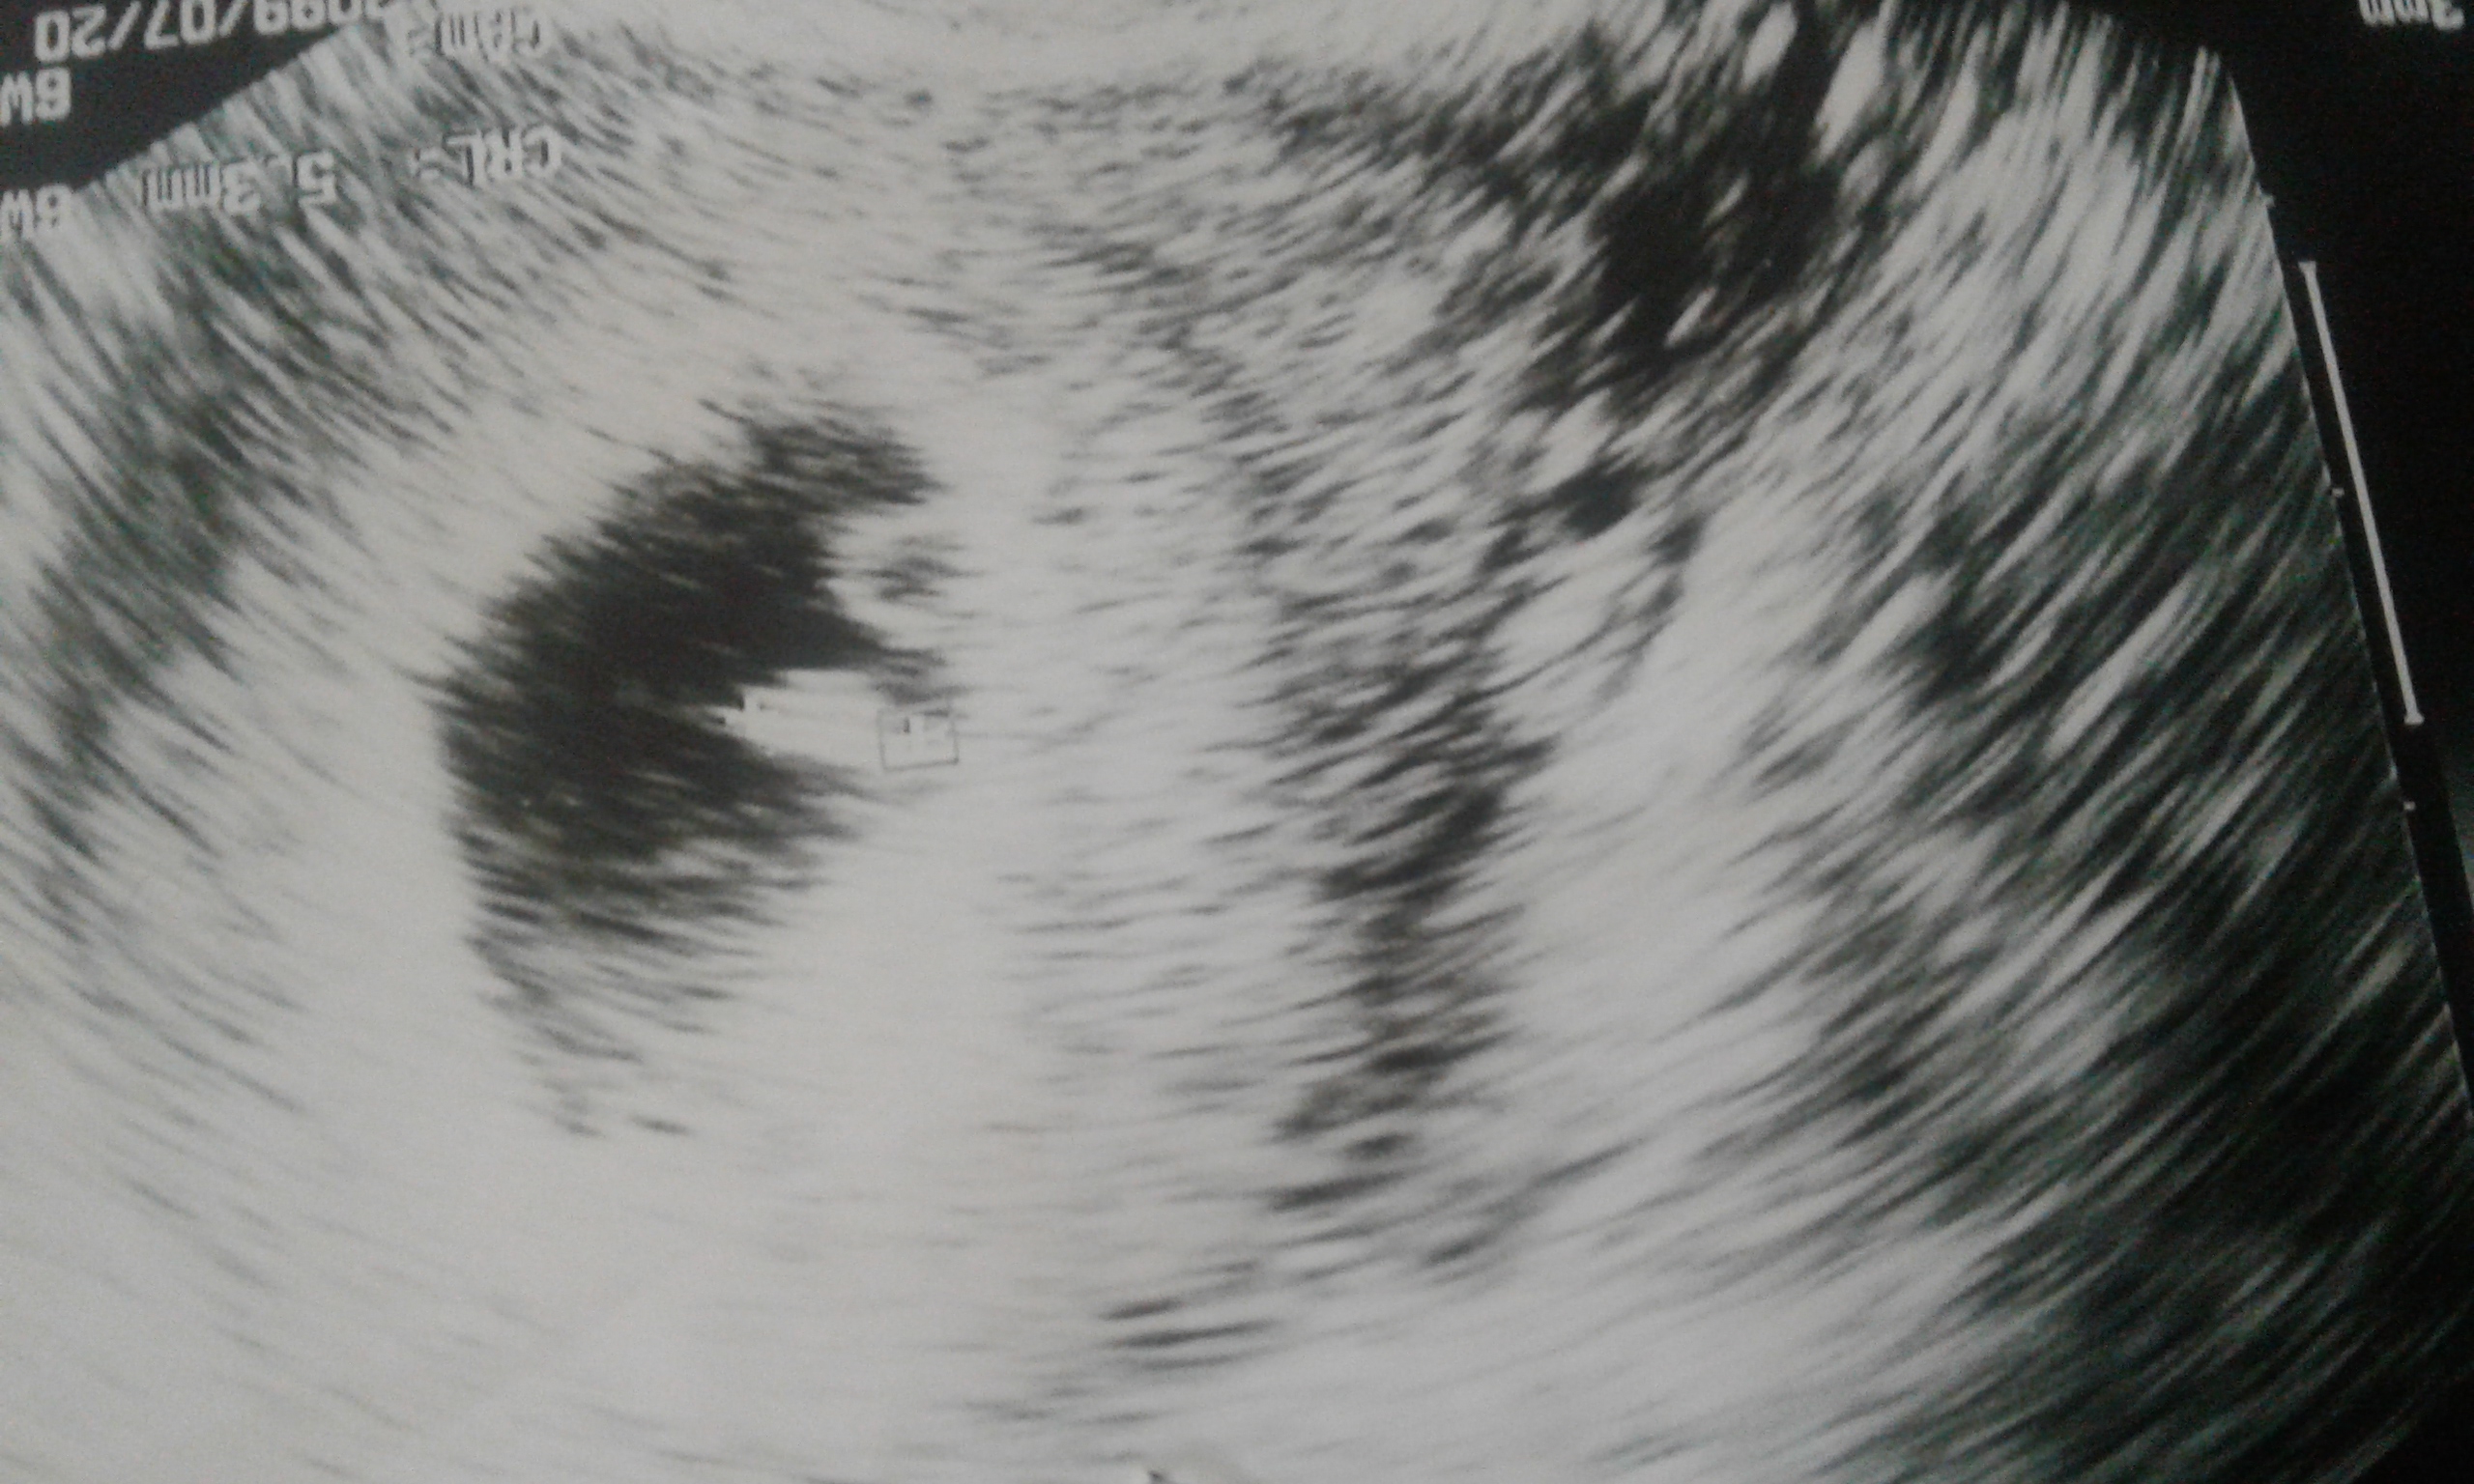

سلام دوستان من هفته۱۳هستم رفتم ان تی گفت احتمال زیاد پسره ؟؟؟؟چون تو دختر اولم رفتم  توی ۱۱هفتگی گفتن پسره بعد تو ی غربالگری دوم گفتن دختره چشمم ترسیده ممکنه اینم استباه گفته باشه یا درسته چون گفت به احتمال زیا د  پسره د دوستان جواب بدن سونو دکتر صلاحی تو نازی اباد رفتم فعلا به هیچ کسی نگفتم چون چشمم ترسیده میشه جواب بدید برای ۲۰اسفند غربالگری دوم زده برام ولی استرس دارم  چرا قطعی نگفت فقط گفت تشخیصم به احتمال زیاد پسره ولی بازم قطعی نمیشه گفت شک افتاد تو دلم  دوستان جواب بدید لطفا

عزیزم احتمال خطا تو ان تی وجود داره . اما اگه سونوگرافی خوب رفته باشی احتمال خطاش خیلی کمه مخصوصا برای پسر .سونوگرافی خوب خیلی شرطه. منم ان تی گفته ۱۰۰ درصد پسره اما آنومالی نرفتم هنوز. من که دلم میگه بچم همون پسره. ببین ته دلت چی میگه.

ولی دکتر خودم میگفت این سونو که من الان رفتم تو منطقه بهترین و جدیدترین دستگاه و داره ....البته دکترمم تو ضربان قلب گفت احتمال۸۰درصد تشخیصم پسره ولی بازم جای خطا داره

اخه بمن درصد نگفت گفت تشخیصم پسره ولی ۱۰۰درصد نگفت گفت احتمال زیاد من تشخیصم پسره ولی بازم تا ۱۶هفتگی صبر کن